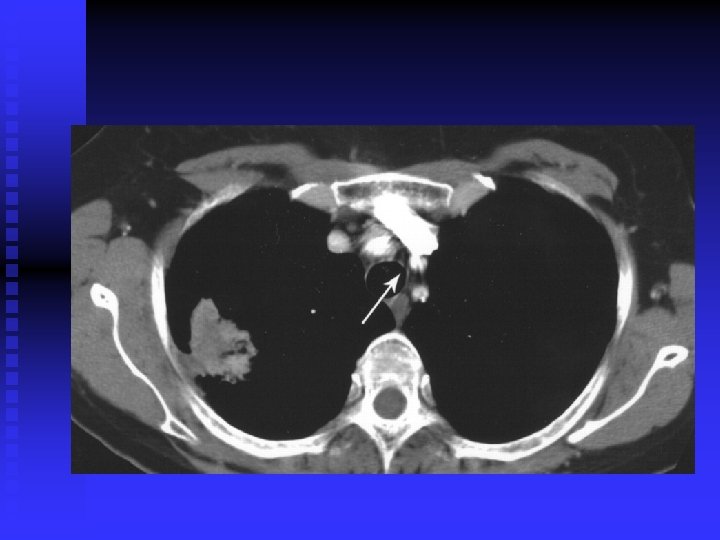

Case 2 40 year old woman, non smoker n Persistent productive cough despite several courses of antibiotics n CXR abnormality: not resolving after several weeks n Admitted to hospital with severe SOB and chest pain n Found to have extensive CXR changes and pericardial effusion n

Case 2 Pericardial effusion drained (pericardial window) n Bronchoscopy and BAL: bronchoalveolar cell carcinoma n Stage 4 disease n Referred for palliative chemotherapy n